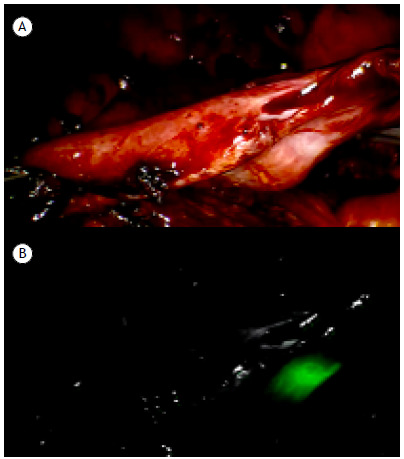

Indocyanine green used in association with a surgical hemostatic agent as a fiducial marker to reduce overflow during robot-assisted thoracic surgery.